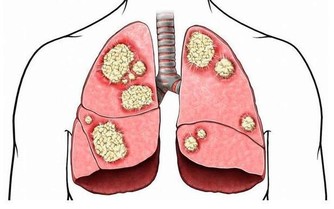

由於糖尿病患者的免疫力較低,容易感冒,

而感冒對人體而言是應激因素,會刺激體內的應激激素升高,從而引起血糖的升高;

感冒若處理不當可引起糖尿病酮症。

因此,糖尿病患者一定要根據氣候變化增減衣服,預防感冒。

因寒冷可刺激體內升糖激素增多,使血糖升高加重糖尿病病情,

而且寒冷可引起血管收縮,使血流減慢,易誘發心腦血管疾病,

所以糖尿病患者要多注意,防“秋凍” 。